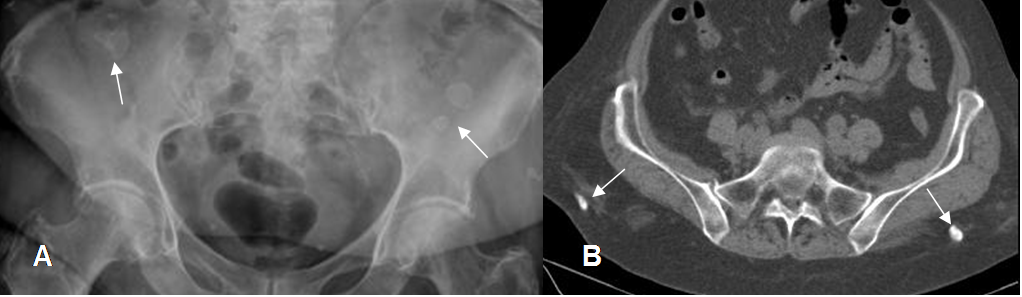

Fig 213. Granuloma.

A: Rx AP y B: TAC axial. Presencia de granulomas calcificados en ambas regiones glúteas.